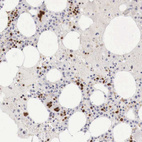

Immunohistochemistry analysis in human bone marrow and pancreas tissues using HPA000232 antibody. Corresponding GATA1 RNA-seq data are presented for the same tissues.